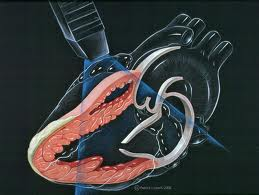

در اکوی دو بعدی تصویر دقیقی از آناتومی قلب ایجاد میشود و در این نوع اکوکاریوگرافی بیشتر برای اندازهگیری اندازه قلب و اجزا و میزان کارایی آنها مورد استفاده قرار میگیرند. از سوی دیگر قدرت عضلانی قلب و بویژه توانایی بطن چپ در بیرون راندن خون از قلب توسط اکوی قلبی قابل ارزیابی میباشد.